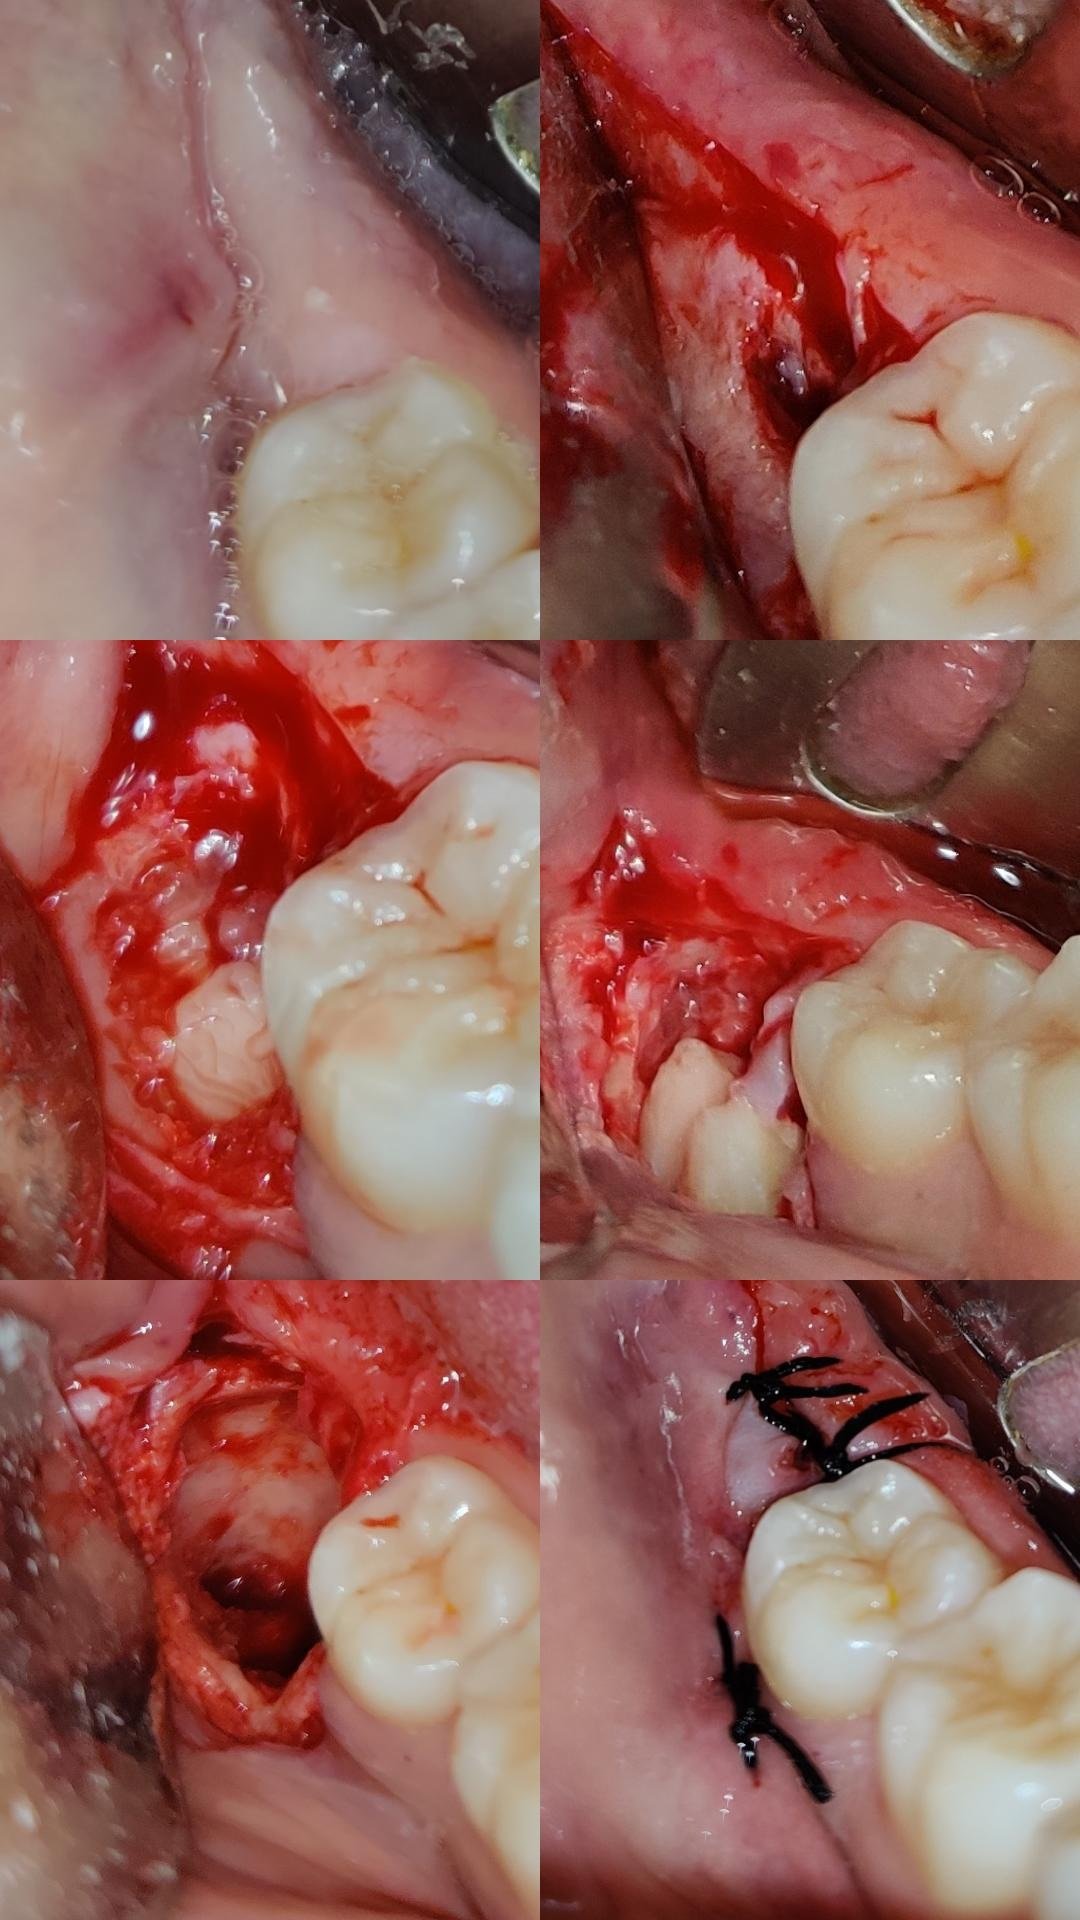

- Dis-Impaction (Wisdom Tooth Removal)

- Surgical Extraction